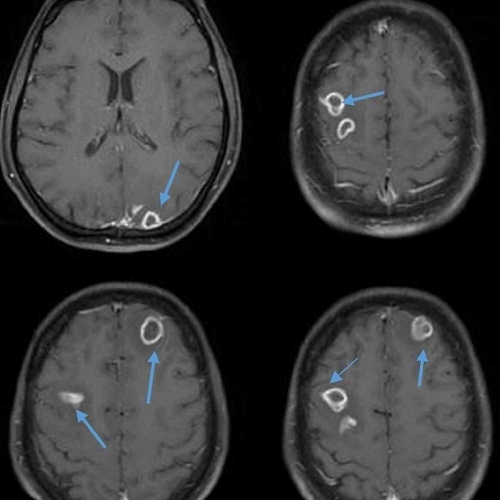

Introduction Brain abscess symptoms in children have drawn attention following a noticeable rise during the winter of 2022, coinciding with...